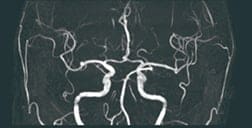

(例) MRA画像から脳動脈瘤の候補点を検出するアルゴリズムの組み合わせ

MRA画像から

血管を抽出